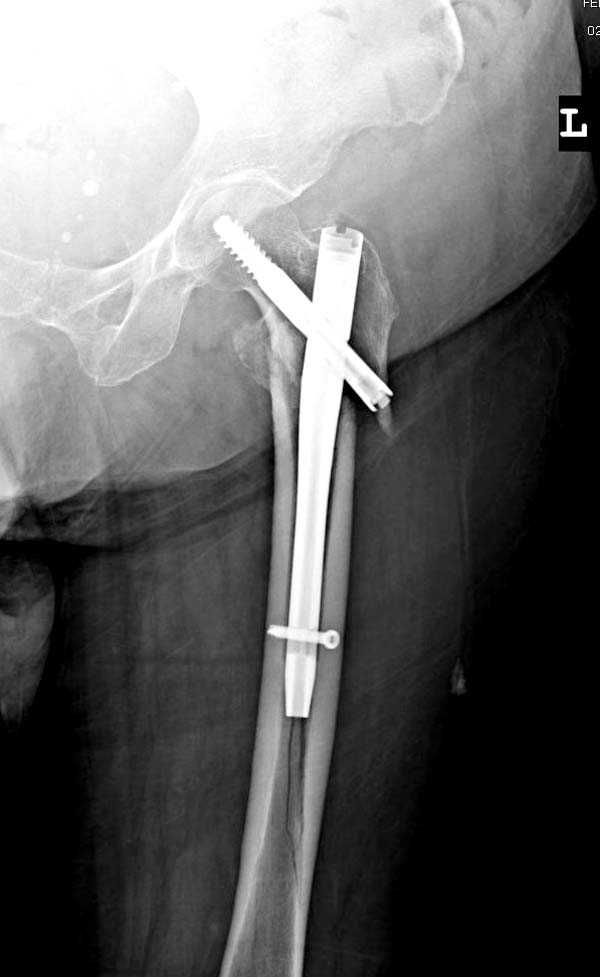

При первом послеоперационном поликлиническом осмотре больная предъявила жалобы на боли в бедре. В серийных снимках обнаружен продольный перелом верхнего отдела бедра.

Считаем, что техническая ошибка произошла во время установки гвоздя, когда рассверливанию канала не уделили должного внимания. Канал остался узковат, и гвоздь был забит с силой. Полная нагрузка конечности приостановлена на две недели, и боли в конечности изчезли. Больная начала нагрузку и перелом срастается.-- Djoldas Kuldjanov, M.D.Associate ProfessorDepartment of Orthopedic SurgerySt. Louis University

Мне тоже представляется, что это не единственная проблема. Продольные трещины заживают легко и быстро. Интересно, почему увеличился варус и

появилась медиализация дистального отломка.

Мне думается, что варусное положение проксимального отломка на последующих снимках не более чем проекционный феномен. Раскол же диафиза вдоль, наверняка, связан с чрезмерно насильственным введением штифта. Вообще, при реверсивных, да и обычных вертельных переломах, многие давно отказались от короткой Гаммы в пользу long-версии. Но в любом случае надо быть на 100 уверенным в подготовке канала.

Перелом А3, подвертельный, вероятно, на длинной версии гвоздя такого бы не произошло